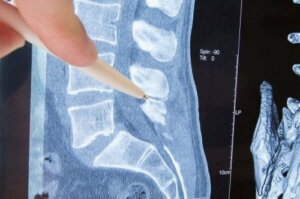

Хребетний стовп або хребет – кісткова структура, утворена хребцями, які, своєю чергою, захищають кістки та дозволяють вільно рухатися. У хребців з кожного боку є отвори, з яких виходять нерви, що йдуть до різних частин тіла.

Частина нерва, яка виходить з хребців, називається «нервовим корінцем». Радикулопатія – це здавлення нерва саме в нервовому корінці. Що її викликає? Які її клінічні прояви? У цій статті ми відповімо на ці запитання та повідомимо про наявні варіанти лікування.